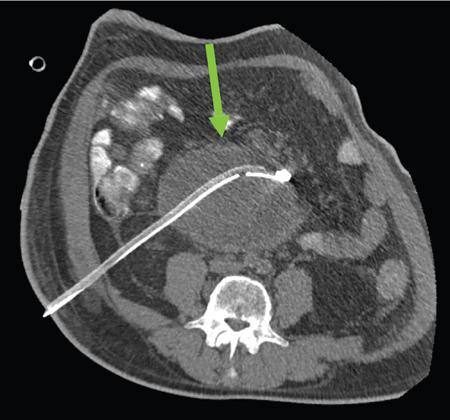

Anirudh Kohli Acute pancreatitis is one of the most dreaded diseases to afflict mankind, in view of its high morbidity and mortality. The single most important factor in reducing the morbidity and mortality of this condition over the last many years has been the role of computed tomography (CT). The incidence of acute pancreatitis is rising especially due to an increasing incidence of gallstones, obesity, as well as an ageing population. Pancreatitis occurs due to a chain of events triggered by a temporary/permanent pancreatic duct obstruction. This leads to activation and release of pancreatic enzymes into pancreatic interstitium and peripancreatic tissues leading to severe auto digestion and necrosis of pancreas and adjacent tissues. Systemically there is release of inflammatory mediators known as cytokines. Tumour necrosis factor is a cytokine which is toxic to acinar cells. These cytokines activate and intensify the inflammatory cascade that may ultimately culminate in multiorgan failure. Clinically severe acute pancreatitis is characterized by two phases, an early phase and a late phase. The early phase is dominated by the systemic effects of release of inflammatory mediators such as cytokines – termed as systemic inflammatory response syndrome (SIRS). Usually there is associated variable multiorgan dysfunction/failure. This phase lasts for a week. When the multiorgan failure lasts 2 days it is termed as mild, multiorgan failure lasting more than 48 hours is considered severe. There is no correlation between the clinical severity of pancreatitis and morphological changes in this early stage. In view of this CT scan is not of much utility during this phase, unless complications are suspected. The later phase is dominated by effects of local complications due to pancreatic/peripancreatic necrosis. Mortality follows this biphasic pattern in early weeks from the systemic effects of multiorgan failure and in later weeks due to local effects, for example infection of necrotic pancreatic/peripancreatic tissues superimposed by organ failure. The Clinical diagnosis of acute pancreatitis requires two of the following three features: If the first two findings are present without any significant SIRS then CT is not required. Acute pancreatitis is a complex disease with a wide variation in the presentation and outcome, ranging from asymptomatic with only biochemical alterations to a fatal outcome. In fact acute pancreatitis is a dynamic disease with continuously evolving appearances on imaging. There are two distinct forms of acute pancreatitis – interstitial oedematous pancreatitis and acute necrotising pancreatitis. Interstitial oedematous pancreatitis is a condition where there is only mild swelling of the pancreas with loss of normal lobulations and a diffuse decrease in attenuation of the pancreas. There may be heterogeneity of the pancreatic parenchyma due to varying degrees of interstitial oedema. This form of pancreatitis runs a mild course and rarely progresses to acute necrotising pancreatitis with its associated complications. In a third of these cases the pancreas may reveal no abnormality on a CT scan. The inflammatory changes may be restricted to the pancreas or extend into the peripancreatic regions. The inflammation in the peripancreatic regions manifests as acute pancreatic effusions. If there is peripancreatic fat necrosis with an oedematous pancreatic gland it is termed as acute necrotising pancreatitis (Figs. 9.17.1–9.17.2). Acute pancreatic fluid collections are enzyme-rich pancreatic juice collections seen in about 40% of patients with acute pancreatitis. The fluid collections occur due to exudation of pancreatic juices into the interstitium of the pancreas and subsequently leakage into the surrounding tissue spaces. These fluid collections are localized only by the anatomic space in which they collect. As the exudative process continues, the parietal peritoneum overlying the pancreas may be disrupted with the inflammatory fluid entering the lesser sac. From the lesser sac the fluid can enter the peritoneal cavity via the foramen of Winslow or by dissecting the peritoneum along the anterior surface of the lesser sac. Posterior extension of the fluid collection in the anterior pararenal space may occur into a potential space between the laminae of the posterior pararenal fascia. Rarely there may be involvement of the perirenal and posterior pararenal spaces. Other pathways of dissection are along the gastrohepatic, gastrosplenic and gastrocolic ligaments. Fluid may dissect along the root of the mesentery into the transverse mesocolon. Collections may extend around the caecum, ascending colon, descending colon and into the lumbar, pelvic and inguinal regions. Large fluid collections may dissect superiorly into the mediastinum or pericardial space. The quantity of fluid in these effusions is variable and can range from a small amount to large quantities (Fig. 9.17.3). Of these collections, 50% resolve spontaneously; the remainder may evolve after 4–6 weeks into pseudocysts. As the collections age, they tend to get localized and walled off, often developing an enhancing wall. A collection should be termed a pseudocyst only when a definite capsule develops and the collection has been static for at least 4–6 weeks. The risk of complications such as rupture, infection and haemorrhage increases with the age of the collection. Large collections of fluid are usually associated with a lesser degree of pancreatic necrosis as compared to extensive pancreatic necrosis associated with a lesser amount of fluid collection. Acute necrotising pancreatitis is a fulminant form of pancreatitis in which there is necrosis of the pancreas, that is nonviable pancreatic tissue. A contrast-enhanced CT is essential as it is the ideal means to demonstrate necrosis as well as to determine the extent of necrosis. These areas of nonviable pancreatic tissue do not enhance as compared to viable pancreatic tissue, which demonstrate significant enhancement. The extent of pancreatic necrosis has been found to correlate extremely well with the extent of necrosis found at surgery. The size, location and extent of pancreatic necrosis are very variable. These areas may be diffuse or focal, small in size to complete glandular involvement. These necrotic areas have a very important bearing on the course of pancreatitis, as they are liable to undergo secondary infection and form pancreatic sepsis. In addition, the more extensive the pancreatic necrosis the greater is the morbidity and mortality. Patients with no pancreatic necrosis have been found to have a 0% mortality and a 6% complication rate, whereas patients with pancreatic necrosis have a 23% mortality rate and an 82% complication rate. A variety of laboratory tests are available to detect pancreatic necrosis, such as a rise in the serum methemalbumin, quantitative estimation of C-reactive protein and urinary trypsinogen-activated peptide. CECT is still the most accurate modality to detect pancreatic necrosis. Pancreatic necrosis may be seen in the pancreas only, peripancreatic tissues also or only in the peripancreatic region. Isolated peripancreatic necrosis occurs due to disruption of the peripheral ductules with extravasation of activated pancreatic enzymes, may be seen in up to 20% of patients who require operative/interventional management of their necrotising pancreatitis. These patients with only peripancreatic necrosis have a better prognosis. This essentially represents retroperitoneal fatty tissue necrosis appearing as heterogeneous areas of liquid and nonliquid components. Over time necrosis evolves and liquefies as well as the liquid component resorbs. Generally if the liquid component is 2 cm or less it will resorb, while fluid collections 5 cm or more rarely resorb. If pancreatic necrosis is not resorbed it may get walled off or with time or may become infected. Encapsulation occurs between the third and fourth weeks. It is important to differentiate sterile from infected necrosis as sterile necrosis rarely needs surgery, whereas infected necrosis requires long-term antibiotic therapy and/or some kind of imaging/surgical intervention. According to the Atlanta 2012 classification, all areas of pancreatic necrosis are termed as acute necrotic collections. This represents a combination of pancreatic/peripancreatic fat necrosis with peripancreatic effusions. On CT, there is a spectrum of findings – solid, liquid containing debris (these may be nonwalled off/partially walled off). Sonography and MRI have advantages over CT scan in demonstration if the contents are pure liquid such as acute pancreatic effusions or have some nonliquefied components such as acute necrotic collections. Pseudocysts are round or oval encapsulated fluid collections containing only liquefied components. It takes 4 weeks for the granulation tissue to develop. On CT, a pseudocyst appears as a well-defined fluid collection with a thin capsule. The most common location for pseudocysts is the lesser sac, though they may be found anywhere in the mediastinum, abdomen or pelvis as they may dissect along fascial planes, along vessels and through capsules of solid organs. Pseudocysts in the bowel, though reported, are relatively rare, as the bowel wall is a strong barrier to the effect of proteolytic pancreatic enzymes. When the contents of the pseudocyst are heterogeneous or uniformly increased in attenuation, the possibilities of infection or haemorrhage should be considered. Focal areas of increased density within the fluid collection usually indicate haemorrhage. Complicated, enlarging or symptomatic pseudocysts require percutaneous catheter or surgical drainage. Infected pseudocysts are treated by percutaneous drainage. The management of a noninfected pseudocyst is controversial. Surgical treatment is only undertaken when the wall is mature after several weeks. Large pseudocysts greater than 5 cm in size can easily be drained percutaneously using intercostal drainage tube or pigtail catheter or endoscopically via the stomach. The cure rates are reported to be 85% with percutaneous drainage, the drainage period averaging about 20 days (Figs. 9.17.4–9.17.5). Walled off necrosis – as pancreatic/peripancreatic necrosis matures and evolves, an interface develops between necrosis and adjacent fatty tissue and an enhancing thickened wall is seen, resulting in a well-defined fluid collection with necrotic debris and fat necrosis. This is the end stage in the evolution of an acute necrotic collection. It is important to differentiate a pseudocyst from walled off necrosis, as a pseudocyst requires drainage and walled off necrosis requires surgical removal (Figs. 9.17.6–9.17.9). Sepsis is a major complication of pancreatitis and is accompanied by a high incidence of mortality and a prolonged hospital stay. Pancreatic sepsis may occur following secondary infection of pancreatic and/or peripancreatic necrosis, acute pancreatic fluid collections and pseudocysts. The only specific sign to demonstrate sepsis is the presence of gas in a collection. This occurs due to secondary infection by coliform/anaerobic organisms. This sign is unfortunately not common and seen in only one-third of cases. Gas is seen in the fluid collection as very dark well-defined air attenuation bubbles. Occasionally gas may be present due to a gastrointestinal fistula or previous surgery. Fat necrosis is seen in peripancreatic collections. This should not be confused with air bubbles, which are indicative of sepsis. The differentiation is easy to understand by CT, the values of fat ranging between – 20 HU and – 80 HU, and of air being >–300 HU. Also air bubbles have well-defined margins and are homogeneously jet black, whereas fat is nonhomogeneously grey with ill-defined margins. Since the presence of air is seen only in a small percentage of patients with pancreatic sepsis, the only other means to diagnose pancreatic sepsis is by CT-guided aspiration. All sites of fluid collection, parenchymal necrosis and peripancreatic necrosis are subjected to CT-guided aspiration. This is a tedious process and requires a dedicated interventional radiologist as there are often more than 5–6 sites from which it may be necessary to obtain samples. A fresh needle and syringe are used for each site, as it is important to know which site has sepsis and which is sterile. Care is taken not to transgress the large bowel as the colon has a large number of bacteria, and transgressing it could result in colonic bacteria contaminating the CT-guided aspiration sample, with falsepositive results. Further, colonic bacteria may be inoculated into a sterile acute pancreatic fluid collection or necrosis thereby converting a sterile collection into an infected one (Fig. 9.17.10). Complications of the procedure can be pneumothorax if the pleura is transgressed, haemorrhage due to trauma to a vessel, and secondary infection. Pancreatic sepsis is treated by surgical debridement, necrosectomy and drainage through thick tubes. It is crucial from the management point of view to differentiate an abscess from infected necrosis. An abscess may be treated by percutaneous drainage, whereas infected necrosis developing in relatively solid tissue can be treated by surgical debridement alone. Imaging-guided percutaneous drainage is the first step in treating pancreatic sepsis especially patients who are very ill and cannot undergo surgery. Initially pig tail catheters were used but these are notorious to get blocked as the largest bore of a pigtail catheter is 12 F. Pancreatic sepsis contains a large amount of necrotic debris, this blocks the catheters can be cleared by flushing the catheter, but this always raises the possibility of introducing secondary infection. To circumvent this issue large-bore ICD catheters have been introduced. These range from 16 F to 30 F. A safe window is necessary, not transgressing bowel or vasculature. It is quite easy to insert these tubes percutaneously under CT. A bit of initial manipulation and force is required to pierce the abdominal musculature. These large-bore drainage tubes have been very effective unless the infected necrosis is solid with minimal liquefied contents or a safe window for placing an ICD catheter is not available. CT is also invaluable in surgical planning and in the follow-up of postoperative patients to evaluate any fresh collection and also to determine whether the drains are well sited or not (Fig. 9.17.11).